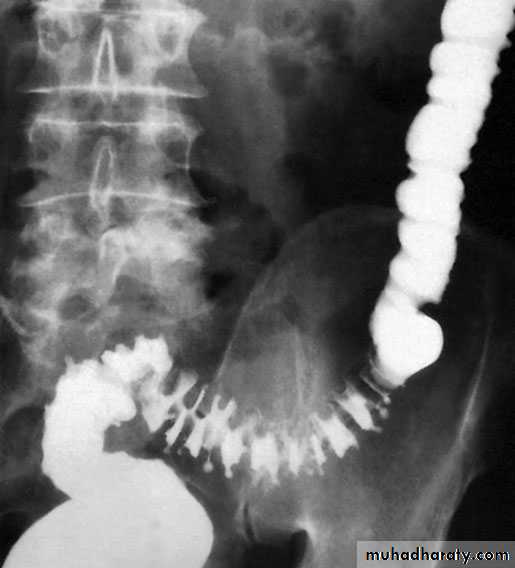

ImagingBarium enema will show similar features to those of colonoscopyin the colon. The best investigation of the small intestine is smallbowel enema . This will show up areas of delay anddilatation. The involved areas tend to be narrowed, irregular and,sometimes, when a length of terminal ileum is involved, theremay be the string sign of Kantor. Sinograms are useful in patientswith enterocutaneous fistulae. CT scans are used in patients withfistulae and those with intra-abdominal abscesses and complexinvolvement .Magnetic resonance imaging (MRI) has been shown to be usefulin assessing perianal disease.

RadiologyA barium meal and follow-through or small bowel enema willshow the absence of filling of the lower ileum, caecum and mostof the ascending colon as a result of narrowing.TreatmentA course of chemotherapy is given. Healing often occursprovided the pulmonary tuberculosis is adequately treated. Anoperation is only required in the rare event of a perforation orintestinal obstruction.

RadiologyA barium follow-through or small bowel enema will show a longnarrow filling defect in the terminal ileum.TreatmentWhen the diagnosis is certain and the patient has not yet developedobstructive symptoms, treatment with chemotherapy isadvised and may cure the condition. Where obstruction is present,operative treatment is required and ileocaecal resection is indicated .